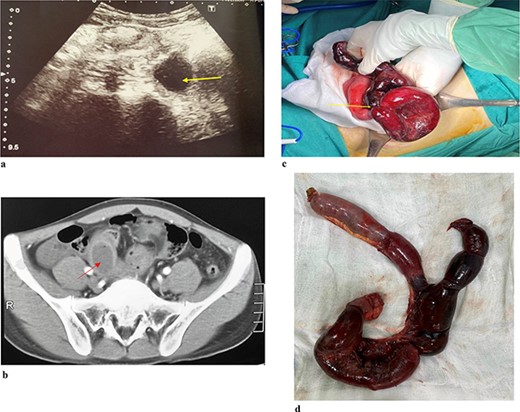

A 21-year-old male patient presented to the emergency department due to colicky right iliac fossa pain with progression to distension, nausea, vomiting, and obstipation. After 72 hours of attempting self-medication at home without any improvement, his family decided to take him to the hospital. During the physical examination, the patient exhibited a body temperature of 39°C, and his tachycardia was 112/min, and blood pressure was 100/70 mmHg. Abdominal ultrasound (Fig. 1) was reported as the right iliac region has an intestinal structure ~81 × 31 mm in size, with a wall thickness of 9 mm and continuous with an anechoic cyst-like structure ~29 × 24 mm in size, with a hypoechoic wall ~5 mm thick. There is little fluid around. CT scan (Fig. 1b) revealed thickening of the small intestinal wall and ileal cyst dilation with bowel ischaemia. Based on the clinical and radiographic findings, he was diagnosed with strangulated bowel obstruction. The patient proceeded to have an explorative laparotomy performed. Intraoperative findings indicated that an isolated tubular ileal duplication had become twisted, resulting in necrosis of the adjacent small intestine extending ~30 cm (Fig. 1c). Surgical intervention involved performing a segmental resection of the bowel and cyst, followed by reconstruction using a side-to-side anastomosis technique. On histopathological examination (Fig. 1d) showed a separation of the ileal duplication cyst. The inner lining of the cyst revealed mucinous epithelium with mucin. He had a successful recovery and was discharged after 7 days.

(a). Ultrasound shows an arrow pointing to anechoic structure with hypoechoic wall. (b) Axial CT scan showing an arrow pointing to an ileal cyst dilation with bowel ischaemia. (c) Intraoperative image of small bowel ischaemia with an arrow pointing to the strangulated location. (d) Postoperative image shows ileal duplication cyst.